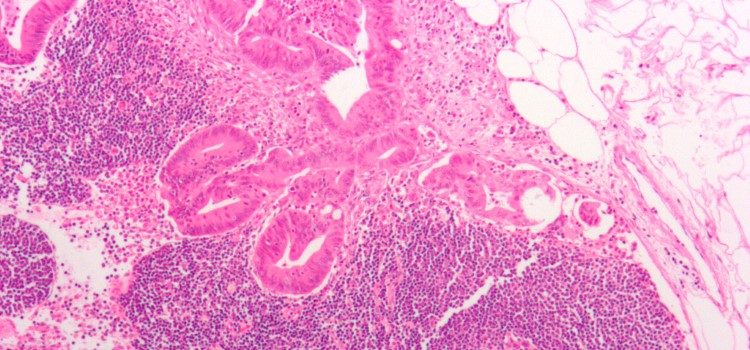

Identificado un factor determinante en las células cancerígenas luminales, causantes del mayor número de cánceres de mama

Una investigación revela con datos en humanos que aquellos pacientes de cáncer de mama luminal con baja expresión de CPEB2 presentan un mejor pronóstico